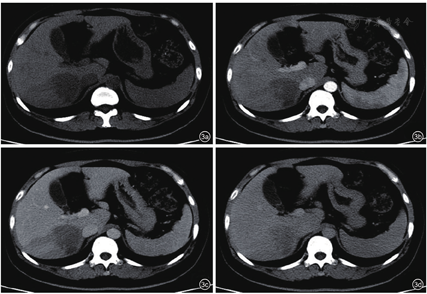

患者,女性,45岁,因糖尿病行体检无意间发现肝右叶肿物3 d入院。无腹痛、腹胀,无寒战、发热,无皮肤、巩膜黄染,无乏力,无体重减轻等。既往2型糖尿病病史,注射胰岛素治疗,血糖控制良好。无肝炎病史,无牧区居住史,无饮酒史,无肿瘤家族史。查体:体温36℃,肝、脾肋下未触及,腹平软,移动性浊音阴性。实验室检查:白细胞计数10.29×109/L,肝功能正常,乙型肝炎表面抗原和核心抗原阴性,甲胎蛋白(alpha fetoprotein,AFP)、糖类抗原19-9(carbohydrate antigen 19-9,CA19-9)及癌胚抗原(carcino-embryonic antigen,CEA)均阴性。腹部超声示:肝脏回声均匀,肝右叶被膜下探及低回声,约5.9 cm×3.6 cm,形态不规则,边界不清,周围无声晕,后方回声未见增强,内未见明显血流信号(图1)。超声诊断:肝右叶肿物,声像图不支持典型肝癌,血管源性病变待排。静脉团注2.4 ml声诺维造影剂,肝脏超声造影示:肝右叶上段可见一大小为5.3 cm×3.4 cm的弱回声团,形态不规则,超声造影呈动脉期高增强,门脉期及延迟期低增强,呈"快进快出"模式(图2)。超声造影诊断:肝右叶实性占位,倾向恶性,建议超声引导下穿刺活检明确性质。腹部CT示:肝右后叶肿物,边界不清,大小约4.1 cm×4.8 cm,分叶状,肿物密度欠均匀,平扫为低密度,增强扫描呈轻度延迟强化,病变侵犯门脉右支分支,致管腔狭窄,管壁水肿(图3),倾向炎性肉芽肿性病变,与肿瘤待鉴别,建议穿刺活检。腹部MRI示:肝右后叶肿物,范围约3.6 cm×4.8 cm,分叶状,边界不清楚,T1加权像(T1 weighted image,T1WI)低信号,T2加权压脂像(T2 weighted image/fat suppression,T2WI/FS)稍高信号影,弥散加权成像(diffusion weighted image,DWI)高信号,增强扫描轻中度延迟强化,病变侵犯门脉右支分支(图4)。腹部MRI诊断:肝右后叶肿物,考虑肝癌可能性大。临床初步诊断:肝右叶实性占位,肝癌待排。患者行超声引导下肝肿物穿刺,组织病理学回报:可见梭形细胞增生,伴炎细胞浸润,结合免疫组化,考虑炎性肌纤维母细胞性病变(图5)。免疫组化结果显示:AE1/AE3(-),Vimentin(3+),Actin(1+),SMA(2+),Desmin(-),s-100(-),CD1a(-),CD21(-),CD35(-),CD68(3+),Ki-67(10%)。患者定期复查,未行治疗。5个月后复查腹部MRI示:原肝右后叶肿物,现已显示不明确,仅局部可见小片状异常信号,T1WI低信号,T2WI/FS低信号,DWI无明显扩散受限,增强扫描强化程度低于周围肝实质(图6),符合良性病变,请结合临床及病理。结合既往穿刺活检及影像学随访病灶消退病史,患者最终诊断为肝脏炎性肌纤维母细胞瘤。随访至今21个月,患者一般情况良好,无复发。

HIMT的超声、超声造影及CT、MRI影像表现多样,可能与不同病灶中病理组织学成分的比例及分布的差异相关[8]。超声常表现为单发、低回声肿块,内回声不均,形态多不规则,在特定切面可呈葫芦状、花生状或多结节融合状等特征性形态,部分病灶周围呈宽带状高回声[9],常无晕环,病灶后方多无明显增强或衰减。由于HIMT中纤维组织增生与慢性炎细胞比例不同,病灶凝固性坏死成分存在差异,随着病程的变化,其声像图表现多样。莫国强等[9]随访7例HIMT病灶发现,3例原低回声病灶内出现高回声,2例原病灶周边低回声晕消失并在11个月后为高回声圈替代,考虑为病变后期或陈旧性病灶内纤维组织增生、形成假包膜所致。本例患者肝脏肿瘤形态不规则,边界不清,与既往报道一致,结合穿刺病理,考虑肿瘤为病变后期,以增生为主。彩色多普勒血流显像(color Doppler flow imaging,CDFI)示肿块内多无明显血流信号,少数内部及周围可探及血流,血流阻力指数(resistance index,RI)多小于0.5[7]。由于不同病灶内新生血管血供程度不同,病灶内纤维化及炎性细胞成分有差异,HIMT超声造影模式亦可呈多样性,但文献报道[10,11],多数HIMT超声造影表现为恶性肿瘤增强模式,即"快进快出",因而超声造影有此模式者并不能完全排除HIMT可能。本例患者肝脏超声造影即因呈现"快进快出"灌注模式而被误诊为恶性。HIMT的CT影像学大多表现为肝内低密度肿块,其强化方式多样,有全瘤填充型、边缘强化型、分隔强化型、无强化型[12]。其特征性改变为动脉期病灶无强化或强化不明显,静脉期及延迟期不同程度、不同方式强化,即呈"慢进慢出"表现,以周边环状强化最多见[13]。本例患者CT表现为边缘延迟强化型,与既往研究相符。MRI平扫病灶多为圆形或类圆形,T1WI常呈低信号,T2WI呈中高信号,推测与病变处于进展期,以慢性炎细胞浸润为主,组织含水量较高有关,MRI与CT强化方式及程度相似,多表现为周边延迟强化[12]。有学者认为,此影像学表现体现了HIMT病理学特点,即病变以门静脉供血为主,肝动脉供血较少[14],病灶门脉期及延迟扫描边缘明显强化,考虑为造影剂从血管内渗透到血管外间隙后,聚集到纤维组织内,从而难以立刻廓清、导致延迟所致[15],病灶中心无强化反映了肿瘤内部细胞可能发生凝固性坏死。本例患者MRI表现T1WI低信号,T2WI稍高信号及周边延迟强化模式,与既往研究一致。HIMT超声造影模式与CT和(或)MRI增强模式不一致,分析可能与造影剂增强原理、从血管渗透途径不同有关。而HIMT在CT和(或)MRI影像学上另一个具有特征性的表现是清晰的门静脉分支可从肿瘤中穿过或包绕,表现为"挂果"征,同时常伴门静脉分支管壁增厚、管腔狭窄,后者为HIMT合并闭塞性静脉炎使门静脉分支受累所致[16]。本例患者CT和MRI均发现病变与门脉右支分支关系密切,MRI误诊为肝癌侵犯门脉右支分支,实则为门静脉右支穿入肿瘤,形成"挂果"征象,门静脉右支管壁水肿、管腔狭窄,实际上形成门静脉炎。HIMT的临床及影像学表现与少血供的肝细胞癌、胆管细胞癌、肝转移癌及肝脓肿有重合,除注意其影像学的特征表现外,还需结合其他因素综合考虑加以鉴别,如全身症状、肝炎和(或)肝硬化背景、肿瘤标记物(AFP、CEA、CA19-9)、既往肿瘤病史等,必要时可行超声引导下肝脏穿刺活检及免疫组化。